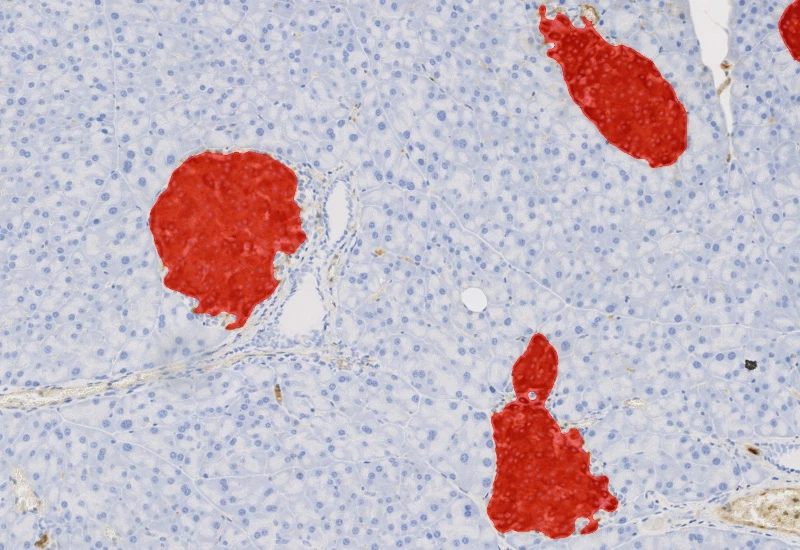

Detect IHC/HC-stained metastructures (e.g. islets, tumor, stroma) and segment single cells into nucleus, perinuclear area, and/or cytoplasm, classify cells inside/outside metastructures, and measure up to 20 intensity, statistic, and morphometric parameters per area and compartment.

insulin islets, pancreas, immunohistochemistry, beta-cells, brightfield

The IHC Meta Cells App combines the detection of IHC/HC stained metastructures (e.g. Langerhans islets, Tumor - Stroma) with single cell detection (segmentation of cells into nucleus, and/or perinuclear area and/or cytoplasm). Detected cells can be classified and visualized as being either within or outside of detected metastructures. Each detected area and cell compartment is measured for up to 20 intensity, statistic and morphometric parameters.

Metastructure detection

Nuclei/metastructure detection